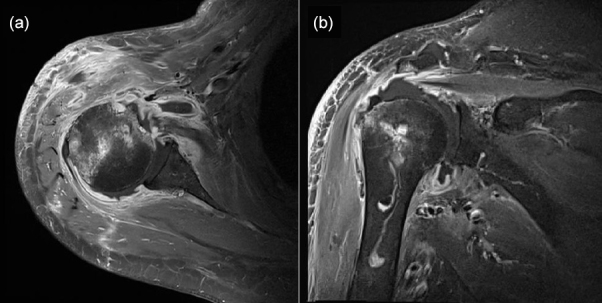

Moraxella catarrhalis commonly colonizes the upper respiratory tract of humans, but infection caused by M. catarrhalis after orthopedic surgery is rare. Here, we report the first case of septic arthritis of the shoulder caused by an M. catarrhalis infection and outline the diagnosis and treatment steps as well as differences compared with other cases.